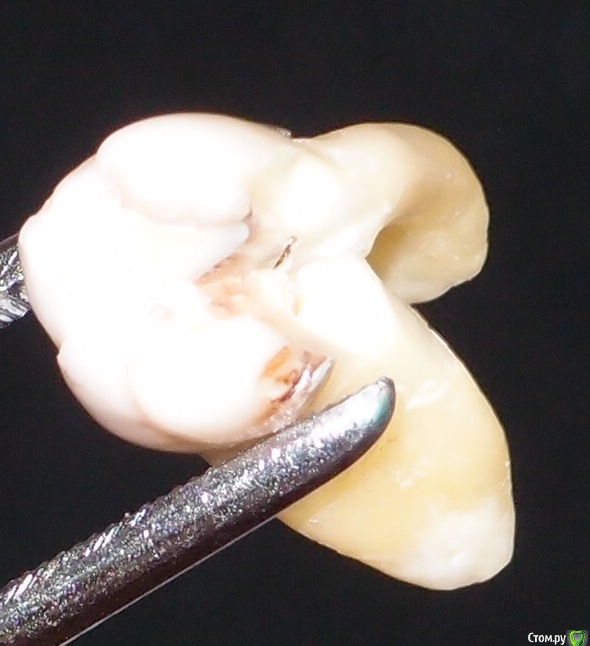

Ирвин Опубликовано 29 мая, 2016 Автор Поделиться Опубликовано 29 мая, 2016 (изменено) Фото покажите Фото зуба, о котором шла речь. Зуб, как вы знаете, удалён. Поэтому фото не во рту. Разрезан был при удалении, не мной. Забрал его без каких-либо задних мыслей. Так всегда делаю, есть ещё два зуба мудрости.В посте об удалении не написал исключительно потому, что не хотел отвлекать внимания от снимка, так как окончательное решение об удалении принималось врачом на основании его. До этого, по результатам визуального осмотра врачом, в ходе которого и произошёл отлом нёбной стенки (на зубе была вертикальная трещина посередине внутренней стороны, она, собственно, и заставила меня этим зубом заняться, всё равно, рано или поздно трещина бы разошлась, плюс ещё повышенная чувствительность поверхности), было принято решение о лечении, так как мне было сказано, что можно поставить пломбу, поскольку граница отлома не уходит под десну. Затем каким-то прибором проверялись нервы на реакцию на пропускание, судя по всему, электрических импульсов. Зуб, а с ним и я, на это никак не реагировали, в связи с чем было сказано, что нервы мёртвые и что это уже плохо, после чего был сделан снимок и принято решение об удалении, так как на снимке, со слов врача, имеется карман с дистальной стороны на всю длину корня и кисты, может быть ещё что-то, я не помню, не специалист. Никакого предложения о том, чтобы сделать диагностическое препарирование зуба не было. Это то, что я могу сказать с точки зрения пациента в части, касающейся принятия решения об удалении зуба. Врач, видимо, изложил свой взгляд и аргументы в своём посте в «Терапии для врачей», я его видеть не могу, но, поскольку, как здесь, в моём посте, так и в теме для врачей, комментарии его коллег явно не его в пользу, как и его (врача) ответы на эти комментарии, особенно ответы, хотелось бы разобраться в ситуации настолько объективно, насколько это возможно. Так как, исходя из её ответов на комментарии профессионалов, у меня теперь складывается впечатление о том, что основными факторами, способствующими принятию решения об удалении зуба было не столько его состояние, а неуверенность в результатах лечения, то, что я не родственник, чтобы биться до последнего и недостаток времени в связи с ожиданием следующего пациента.Если пугала ответственность, логичнее было бы отказаться от лечения вообще и отправить к более опытному врачу, чем упрощать процесс до удаления. Последние две причины вообще за гранью моего понимания. Хорошо, что врач не хирург и речь о зубе, а не о руке или ноге. Ещё раз всем спасибо за комментарии! Изменено 29 мая, 2016 пользователем Ирвин 1 Ссылка на комментарий

M@estro Опубликовано 30 мая, 2016 Поделиться Опубликовано 30 мая, 2016 (изменено) Судя по фотографии, удаление было проведено максимально бережно , с разделением корней, так что это уже хорошо ) По фото вижу достаточно обширный поддесневой дефект твердых тканей зуба, практически критический. Думаю, что объективно картина была более понятна. Теперь могу дать совет - тщательно выбирайте команду имплантолог - ортопед. Успехов ! Не расстраивайтесь , зуб не 100 % спасаемый, зачастую удаляют гораздо более спасаемые зубы "без суда и следствия" .P.s. То , что зуб разрушен язычно - очень нехорошо, это резко ухудшает прогноз реставрации. Изменено 30 мая, 2016 пользователем M@estro 6 Ссылка на комментарий